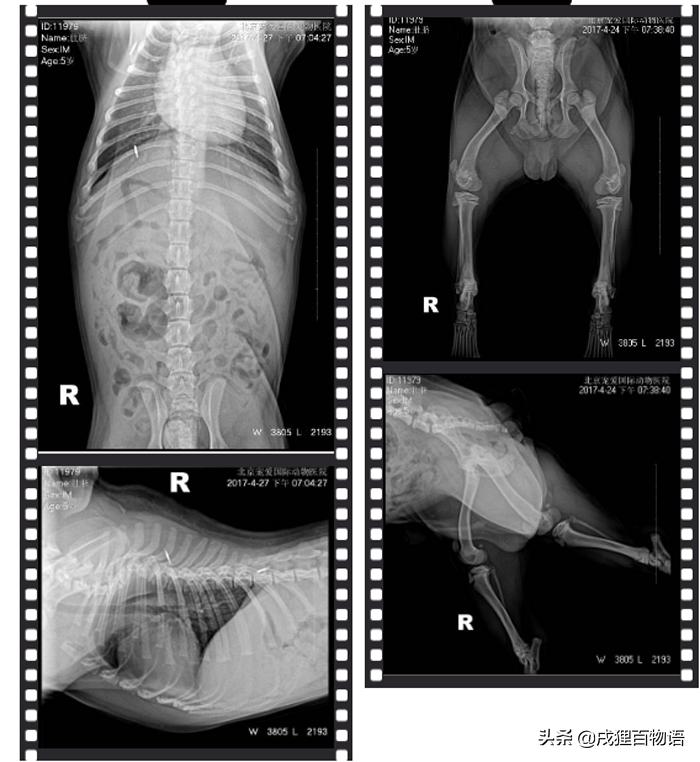

(1) DR显示T4-T6发育异常,但不排除未骨折造成

(2) MRI显示T2-T6椎体畸形,脊髓受到压迫并伴有水肿

医生诊断肚脐为T4-T6椎体畸形,脊髓萎缩。